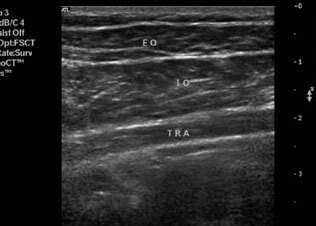

Ultrasound Diagnostic Imaging

Ever feel like you need to know for sure what is going on inside your body...

• ​Ultrasound diagnostic imaging is the premiere diagnostic tool to evaluate soft tissue injuries.

• ​Ultrasound allows us to see your muscles working in real-time, not just a static picture, like MRI or x-ray.

• In our Level Up program we complete diagnostic imaging right in the treatment room, within minutes we can confidently assess your injury and determine if any additional referral is needed for advanced care.

• ​No need to go to multiple doctors office or wait for expensive MRIs to feel confident that you are making the right decision with our prescribed therapy program.

Real Time Ultrasound Biofeedback

Ever wonder if you are doing an exercise correctly and changing the target muscle...

• ​Learning a new movement pattern and creating new muscle memory is challenging.  Imagine how much quicker you will learn a different muscle sequencing pattern when you can what an ideal contraction sequence looks like in real time on a screen in front of you.

• ​Never again will you wonder if you are doing the exercises prescribed by your therapist correctly.

• ​Get the most out of the time you spend exercising at home with the LEVEL UP program.